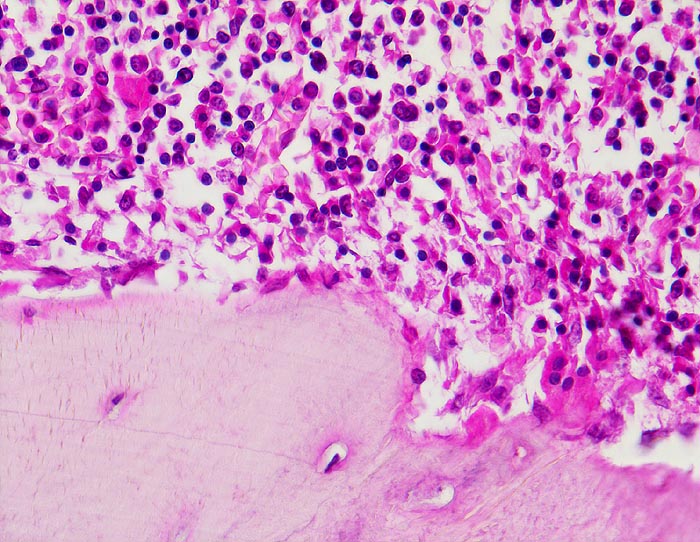

• Linker Wirbelkörper mit Osteoporose, rechts ein normaler Wirbelkörper zum Vergleich.

• Deutliche Rarefizierung und Atrophie vor allem der horizontalen Spongiosabälkchen.

• Hochgradige Reduktion der intertrabekulären Vernetzung.

• Reaktiv hyperplastisches blutbildendes Mark.